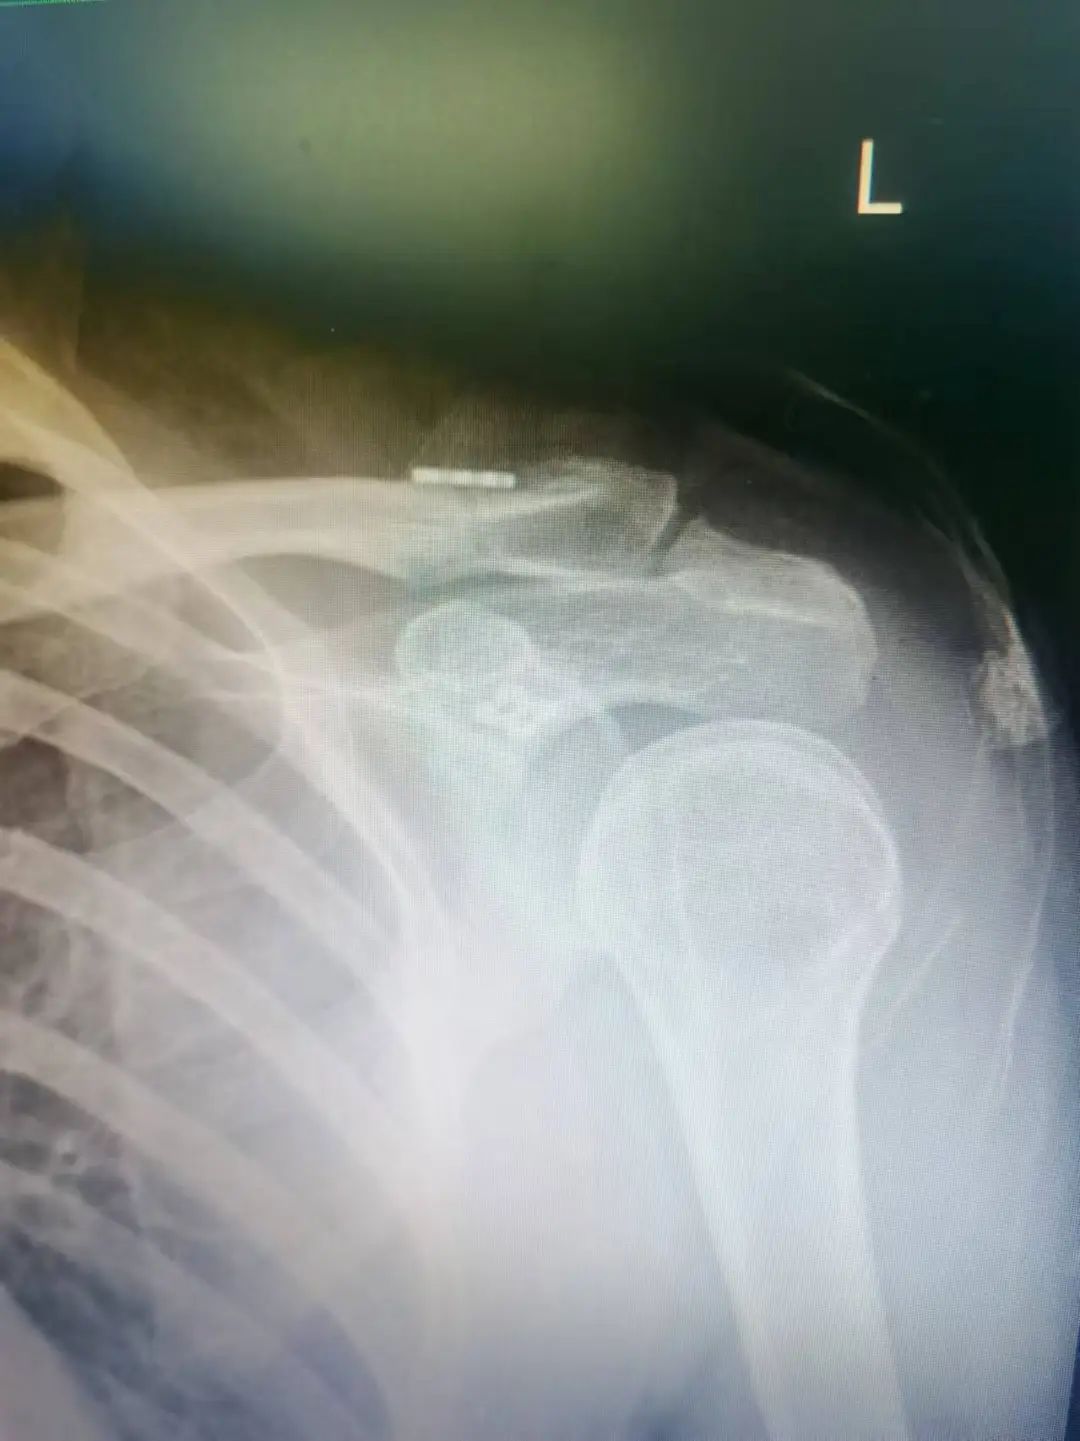

術后圖片

按壓鎖骨遠端復位,自肩峰外鉆入一直徑2.0克氏針臨時固定肩鎖關節應用專用定位器,距肩鎖關節3cm處自鎖骨中后三分之一向喙突基底部鉆取骨道后,引入帶袢鈦板,收緊主線,打結固定,拔除克氏針,C臂透視證實肩鎖關節復位良好。